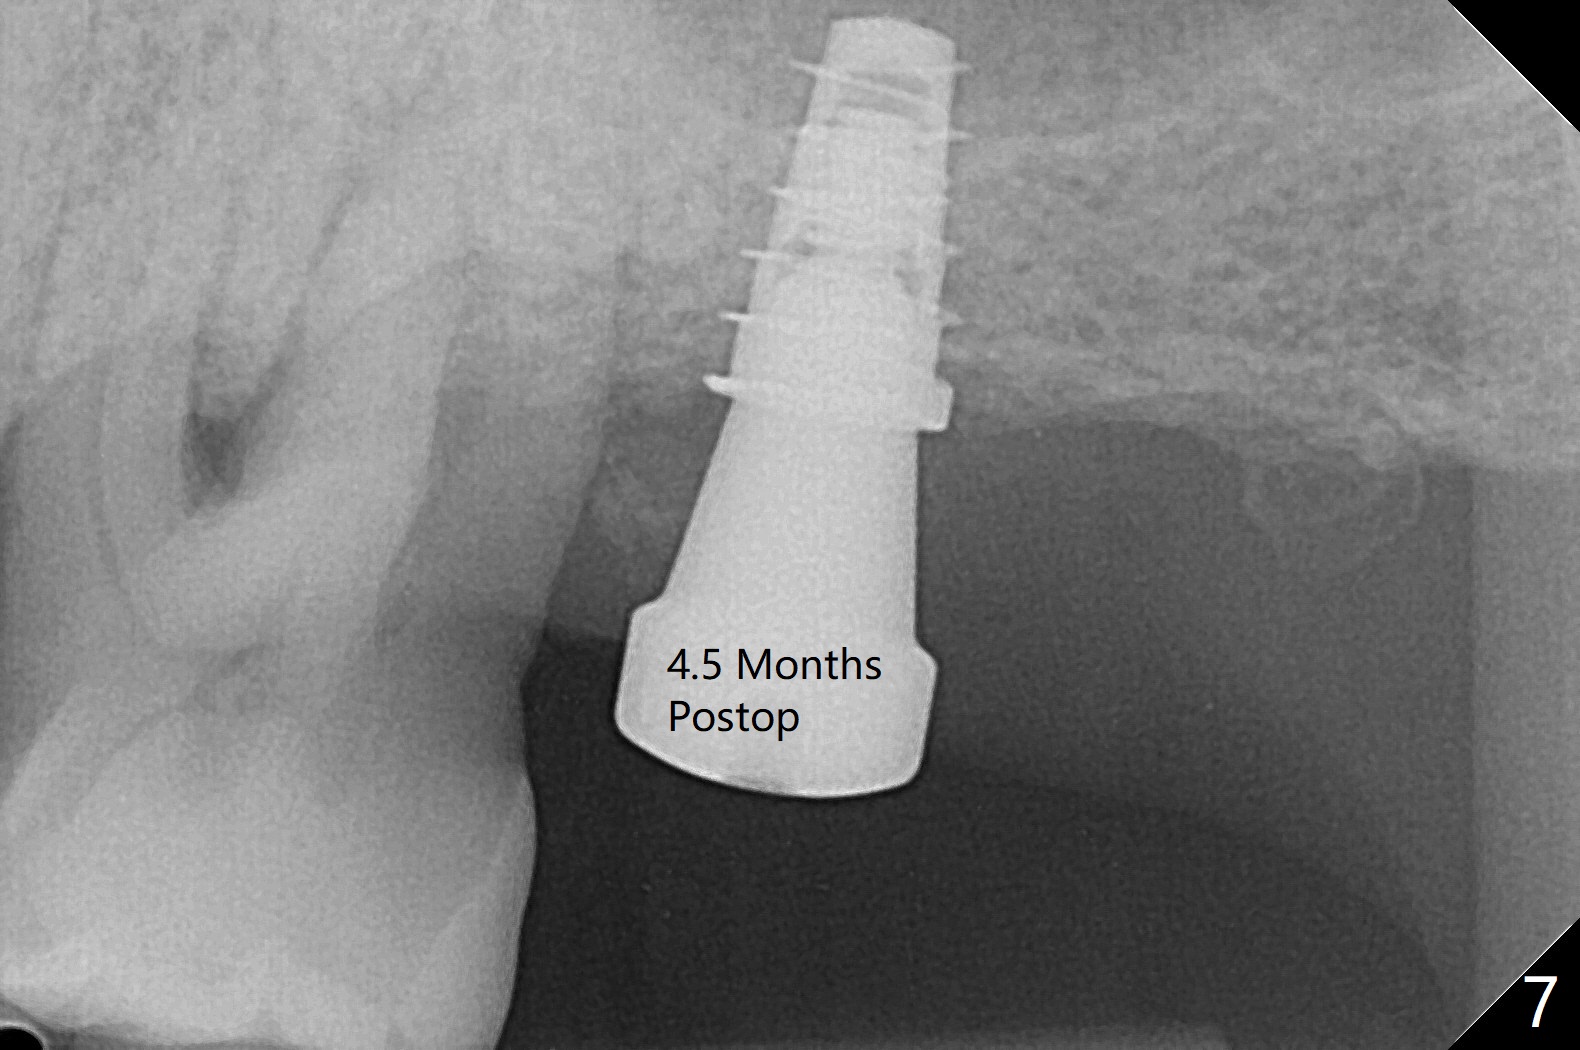

Bone在上颌窦里凝固了。其实左侧上颌窦粘膜术前增厚(图四,五:L),人工骨仿佛弥撒在上颌窦膜中(图六)。术后一周病人没有任何鼻窦症状。术后4.5月旋转愈合基台时,病人感到疼痛,终止取模(图七),两个月后复诊,做progressive loading。术后5.5月旋转愈合基台时,植体一起出来,但是上颌窦膜没有破,放置大一号植体(报废)扭力不够(图八),再大一号扭力可以(图九),放置愈合帽。由于邻牙长(图九:双箭头),牙周敷料逗留三周不掉(图十:P)。撤除后,伤口愈合正常。The

7